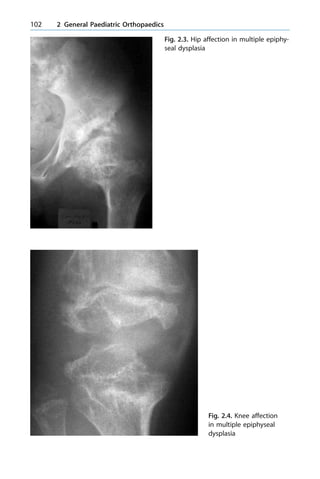

sports, such as athletes

3.6.6.2 Percutaneous Cannulated Screw Fixation

n Advantages:

± Earlier return to work